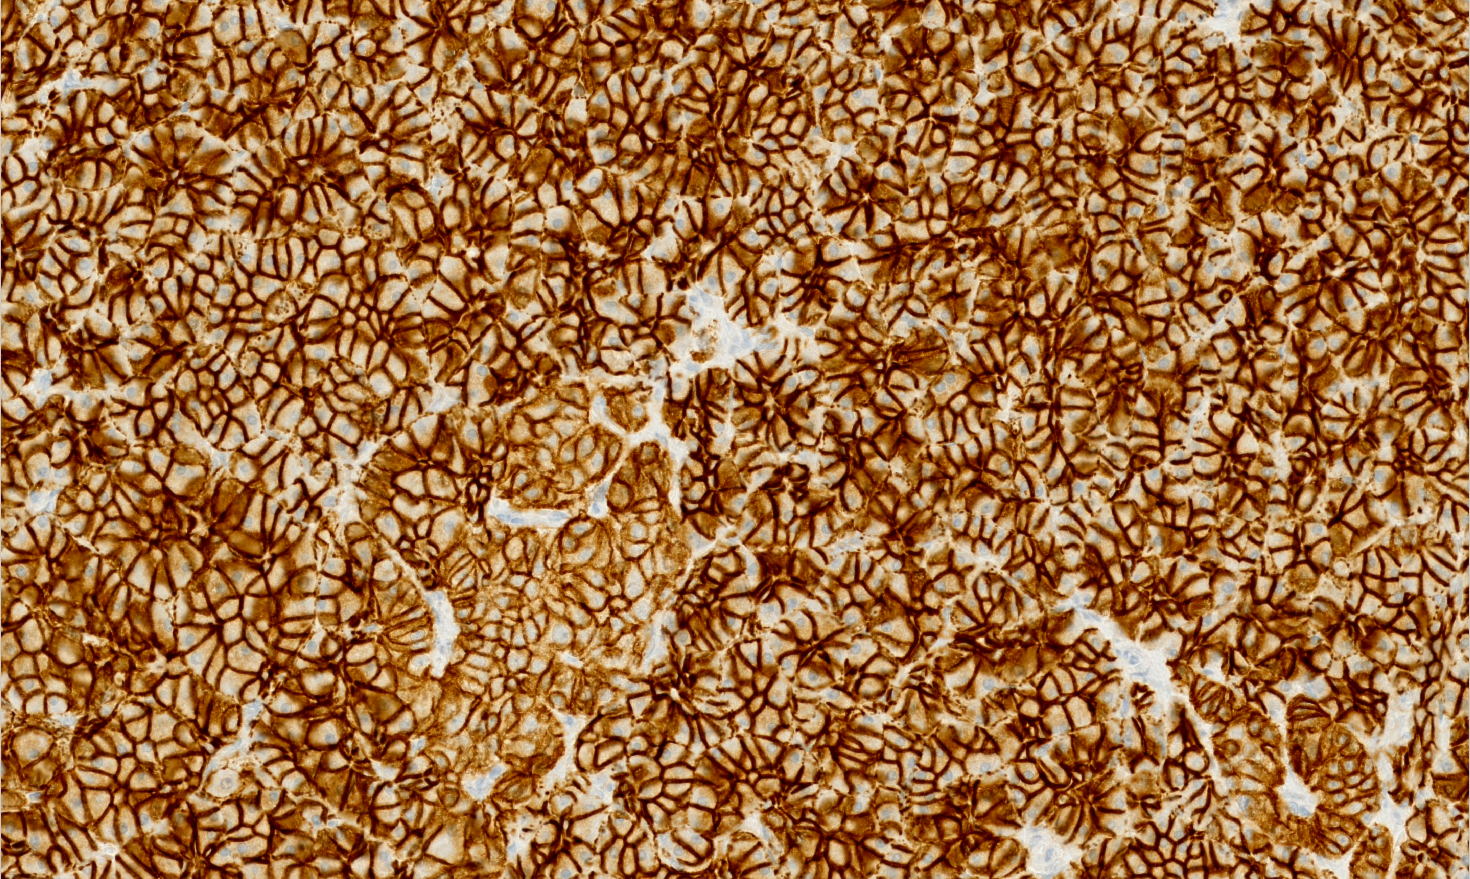

Los escáneres o digitalizadores de láminas son microscopios automatizados capaces de capturar imágenes digitales idealmente en alta resolución a partir de láminas histológicas físicas. Existen distintos modelos según el volumen y la aplicación clínica, pero para diagnóstico deben cumplir estándares estrictos de calidad y precisión.

Digitalizamos tus láminas y entregamos archivos listos para diagnóstico, revisión o docencia, con imágenes de alta resolución que cumplen estándares internacionales y que pueden ser fácilmente integradas por sistemas LIS.